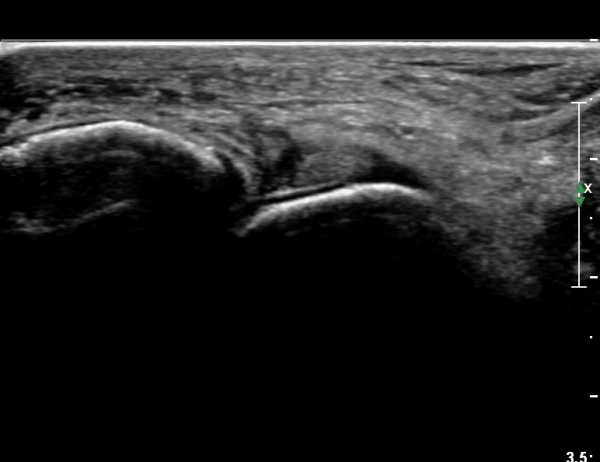

Àü°ÅºñÀδë Á¾´Ü¸é°Ë»ç¿¡¼­ Àü°ÅºñÀδëÀÇ ÆÄ¿­ÀÌ °üÂûµÈ´Ù(»çÁø 4, 5).

Àü°ÅºñÀδë Àü¹æ°ßÀΰ˻翡¼­ ÀÎ´ë ÆÄ¿­¿¡ ÀÇÇÑ °Å°ñÀÇ °úµµÇÑ ¿òÁ÷ÀÓÀÌ °üÂûµÈ´Ù(µ¿¿µ»ó Âü°í)